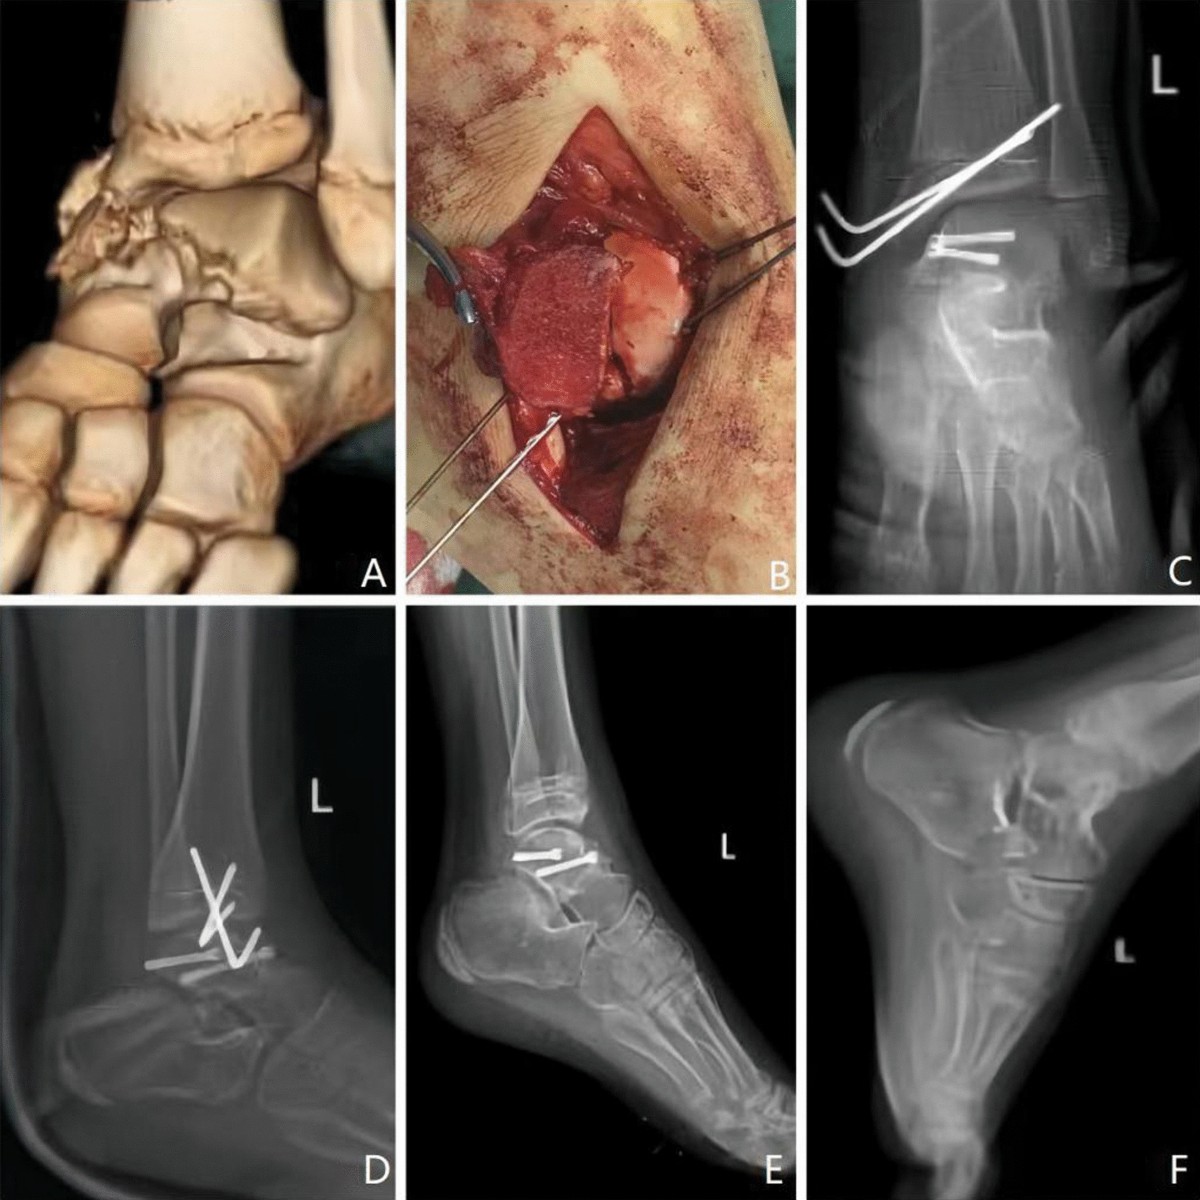

talus fracture

Talus fracture (95) 사진

Talus fracture approach (95) 사진